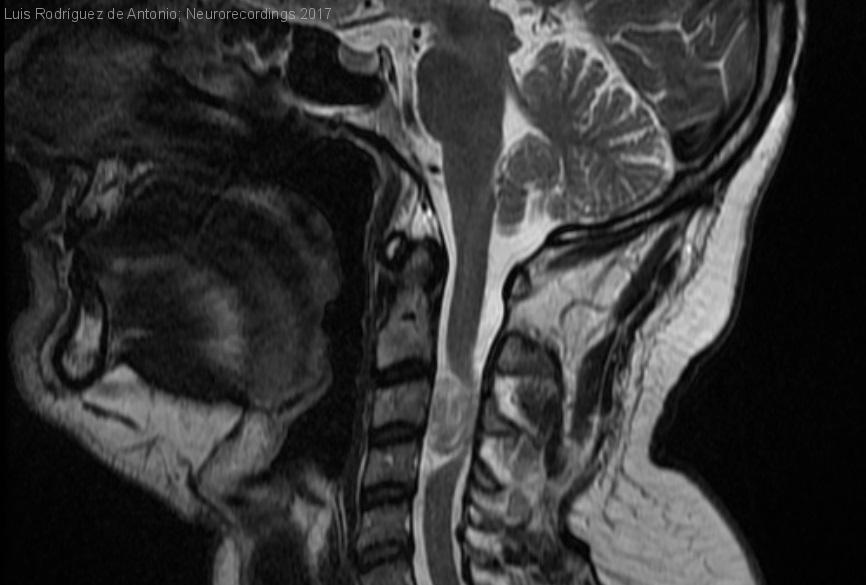

Hombre | 43 años

Diagnóstico final: Schwannoma cervicomedular aislado

Varón de 43 años que consulta por dolor cervical irradiado hacia el brazo y la mano izquierda, junto con debilidad y parestesias en la mano de un año de evolución. En la exploración física se...